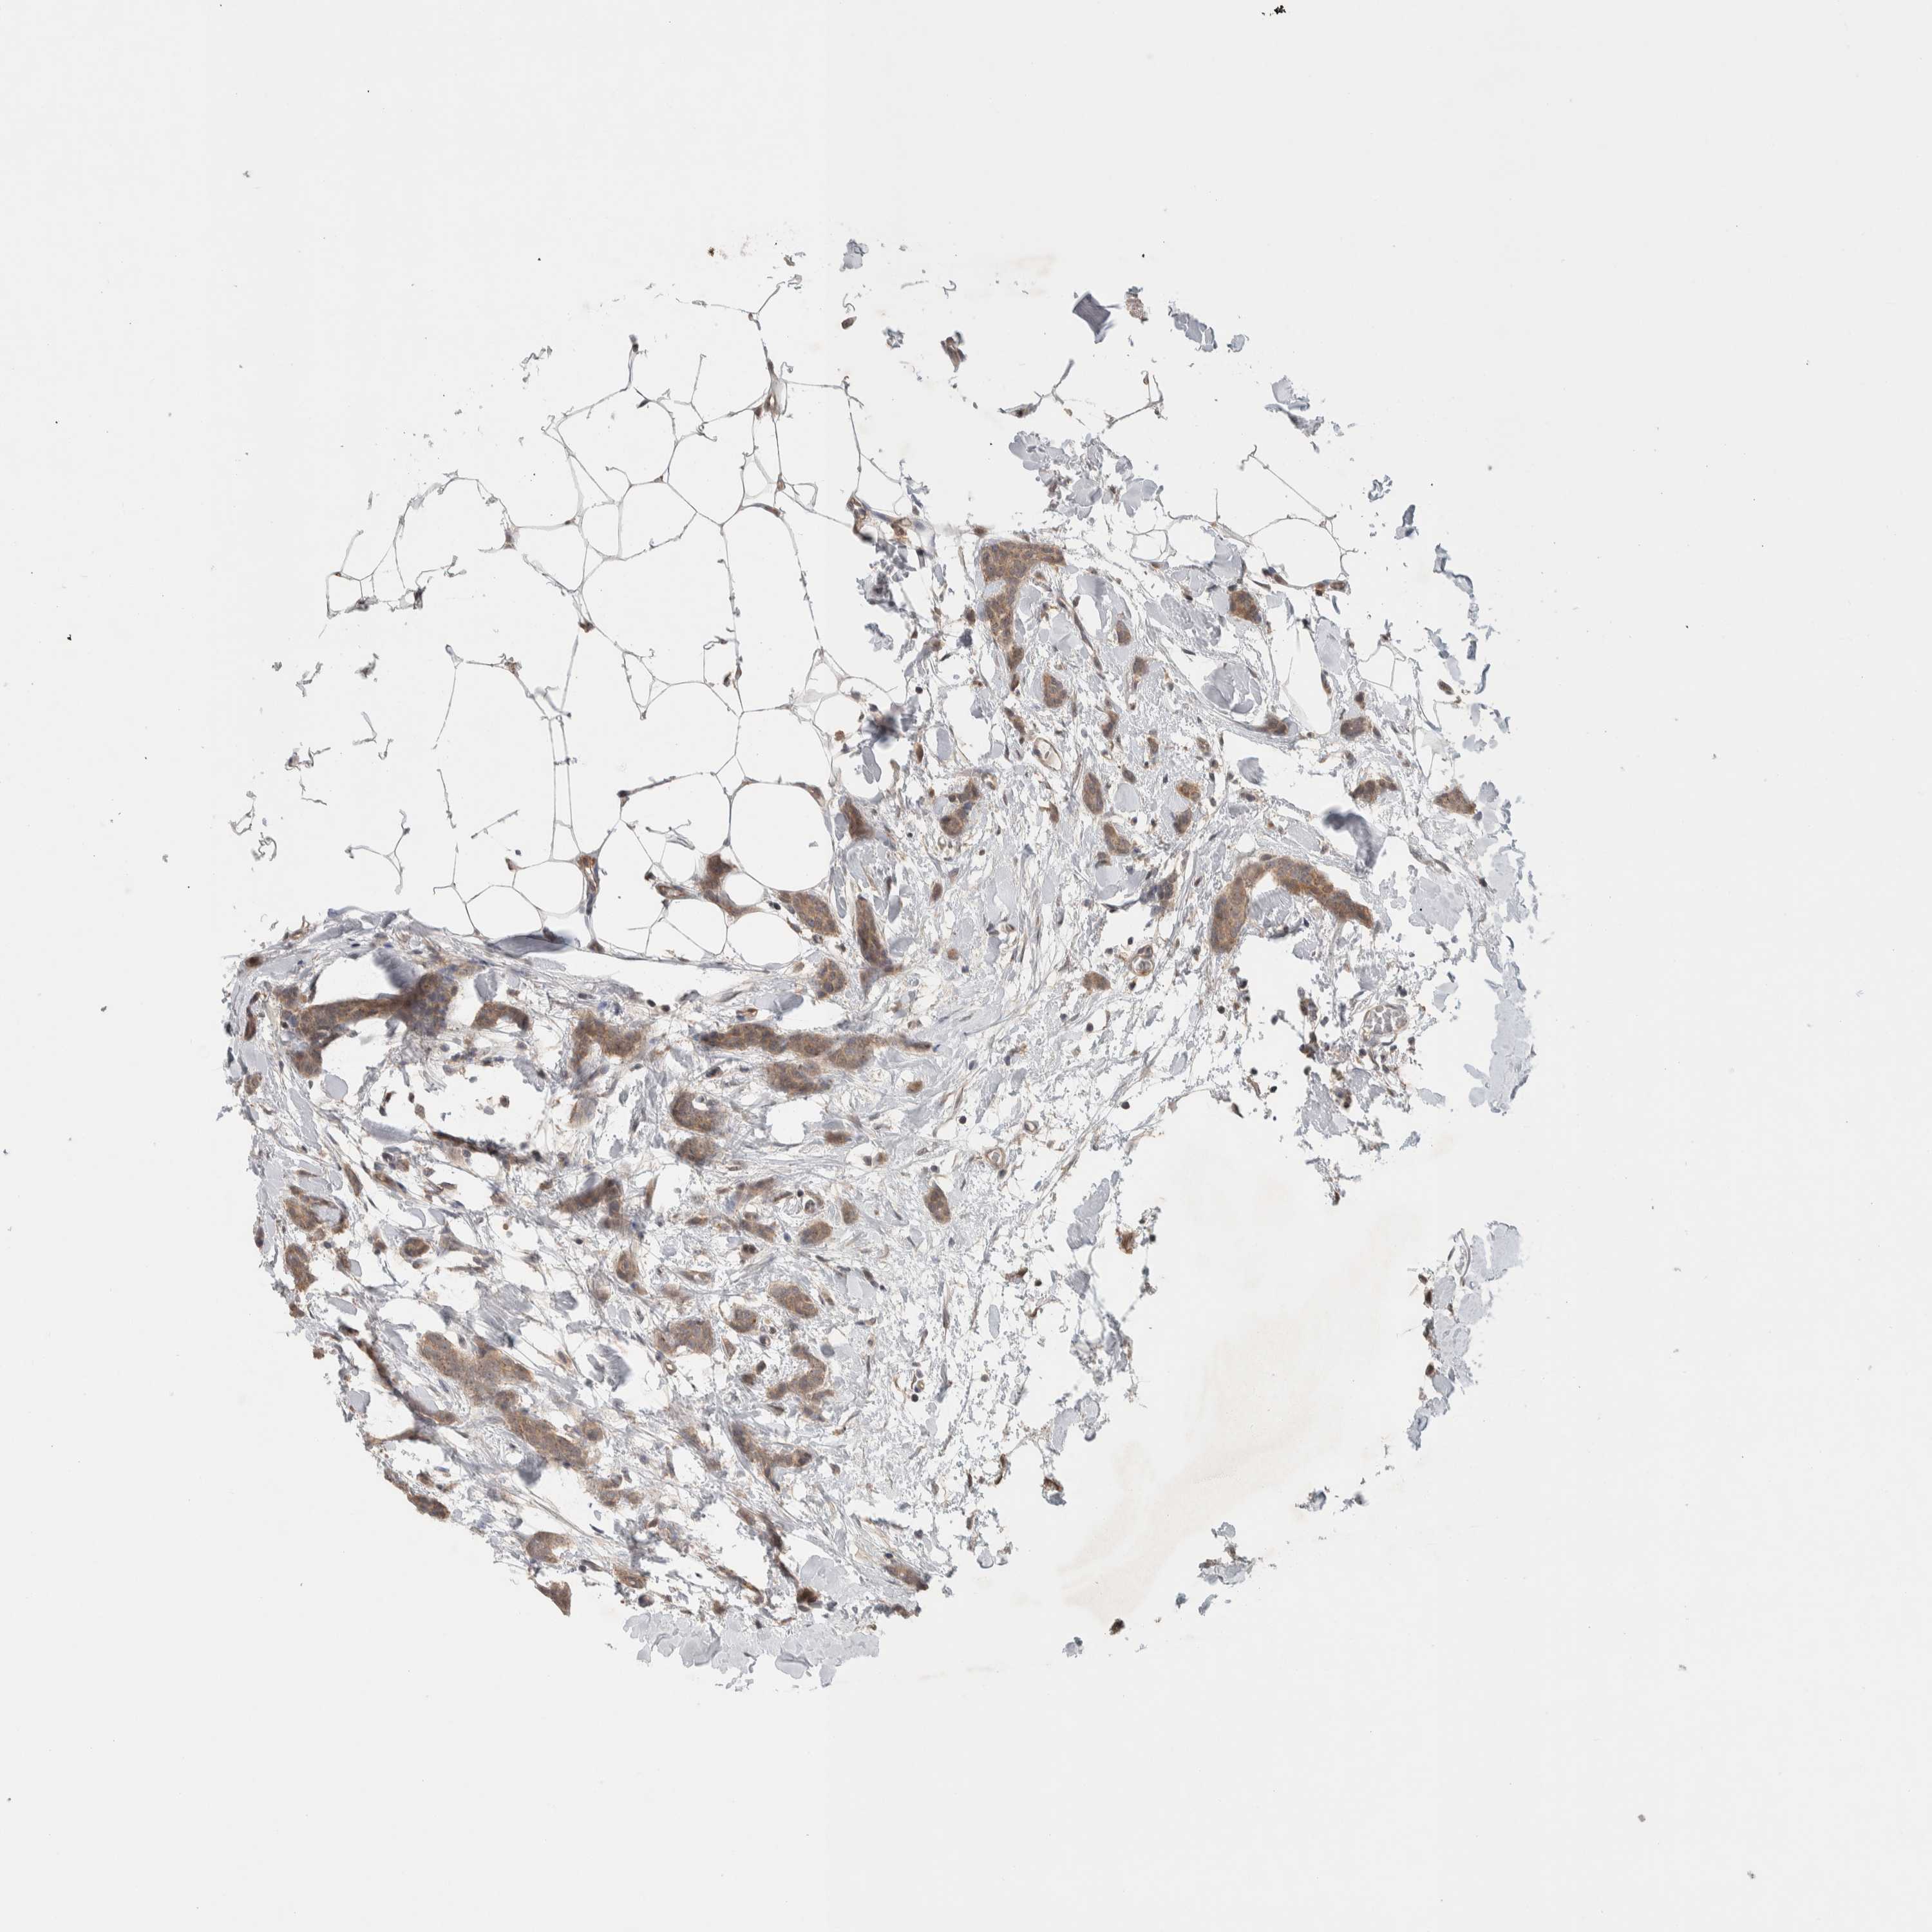

BRCA TCGA BRCA VALIDATION PROTEIN EXPRESSION